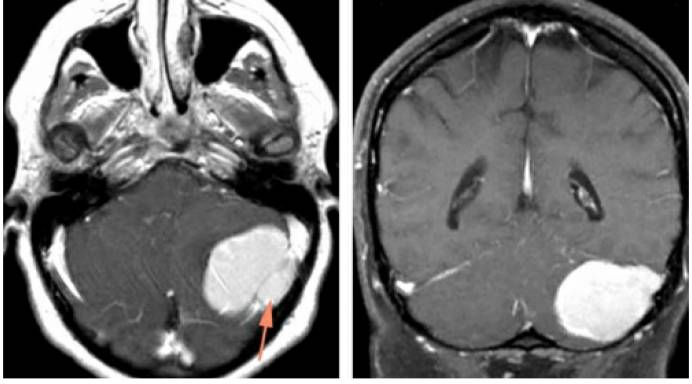

图15:如图所示为1例左侧小脑凸面脑膜瘤,注意肿瘤已侵犯到窦内(左图箭头所指),部分横窦节段已完全闭塞,MRV也证实了横窦局部的闭塞。最终该肿瘤被全切,受侵犯的窦也通过磨除横窦上下方骨质后一并切除,并使用两根丝线结扎其与正常横窦的分界处。同时,labbe静脉汇入至横窦的入口保留完好。